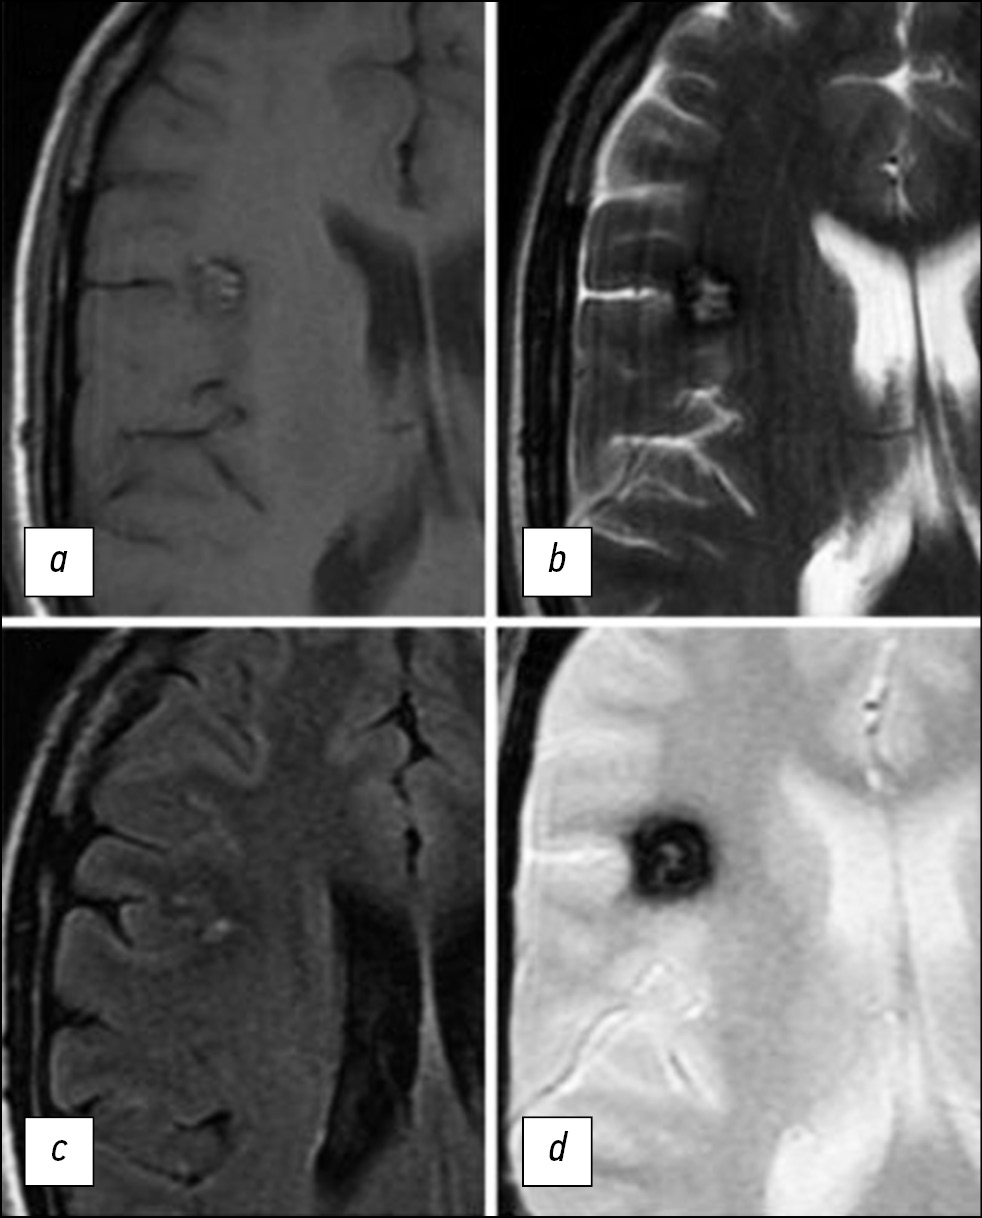

Hemosiderin deposits in and around the CM are considered a typical sign of repeated subclinical hemorrhages or erythrocyte lysis; they provide magnetic susceptibility to this pathological lesion, especially at a high-magnetic-field strength. The heterogeneity of the magnetic field in the presence of hemosiderin also contributes to the differentiation of blood flow and the effects of hemosiderin in CMs (Fig. 2) [16, 17].

Fig. 2. MR images of the brain in the axial view in the T1–WI (a, c), T2–WI (b), and T2*GRE (d) modes demonstrate a more detailed visualization of the CM structure (the same case as in Fig. 1). The images show a focal lesion of a characteristic cellular structure with a hypointensive peripheral signal on T2–WI. The T2*GRE sequence emphasizes the florid effect of hemosiderin.

The combination of a reduced signal rim with a reticular nucleus of mixed hyper- and hypointensity on T2–WI with a high probability is a diagnostic sign of CM. For smaller CM lesions, a point area of hypointensity is assessed on T2–WI. Vasogenic edema accompanies lesions in perifocal regions, which are indicated by an increased signal intensity on T2–WI, and the mass effect usually does not appear even with a sufficiently large lesion if no relatively recent bleeding has occurred (Fig. 3) [17, 22].

Fig. 3. T2*GRE image in the axial view shows a large cavernous angioma in the left occipital lobe. Despite the significant size of the lesion, no perifocal edema and mass effect on the surrounding structures are found.